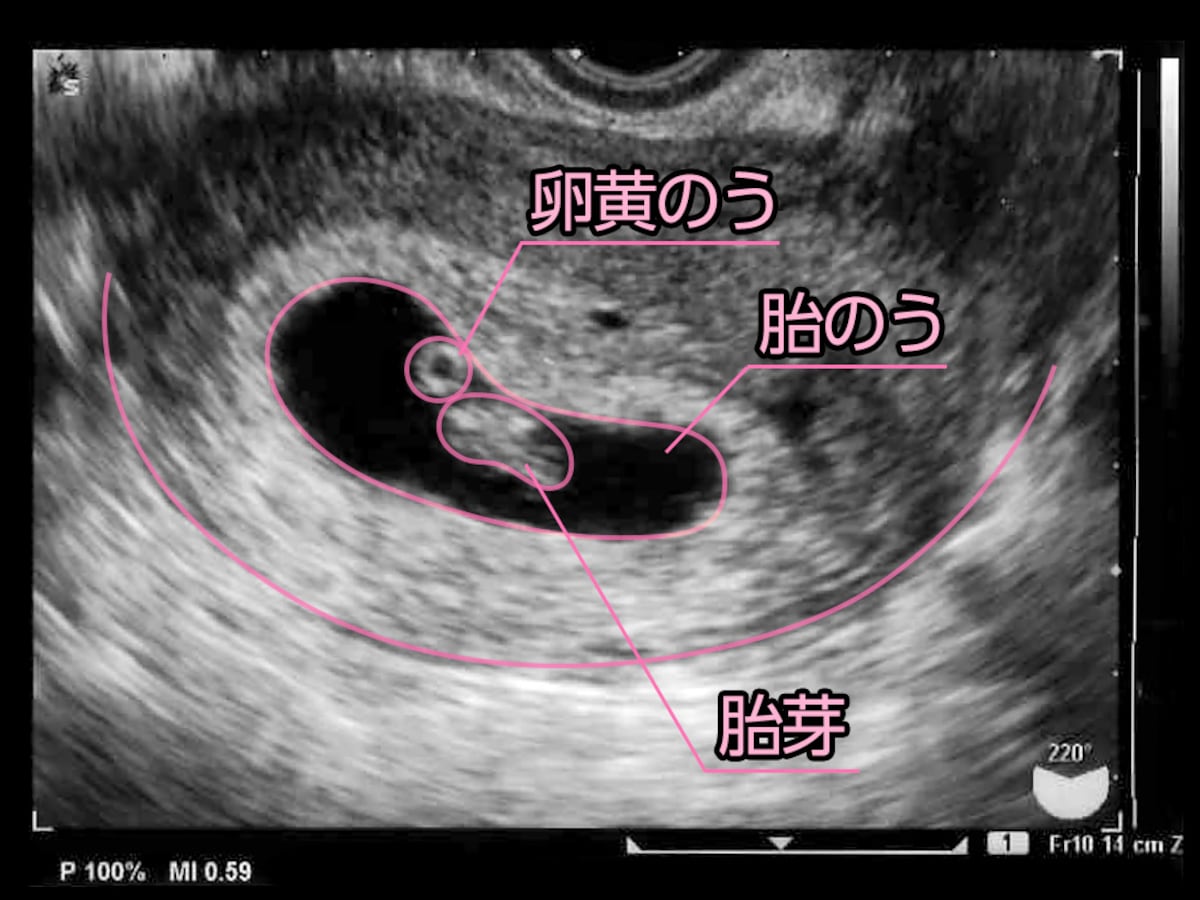

5 産科一般超音波検査 初期編 正常所見4 7週 日本産婦人科医会

妊娠2ヶ月 妊娠4週0日 7週6日 の胎芽の超音波画像 2 超音波画像で見る妊娠各月の胎児